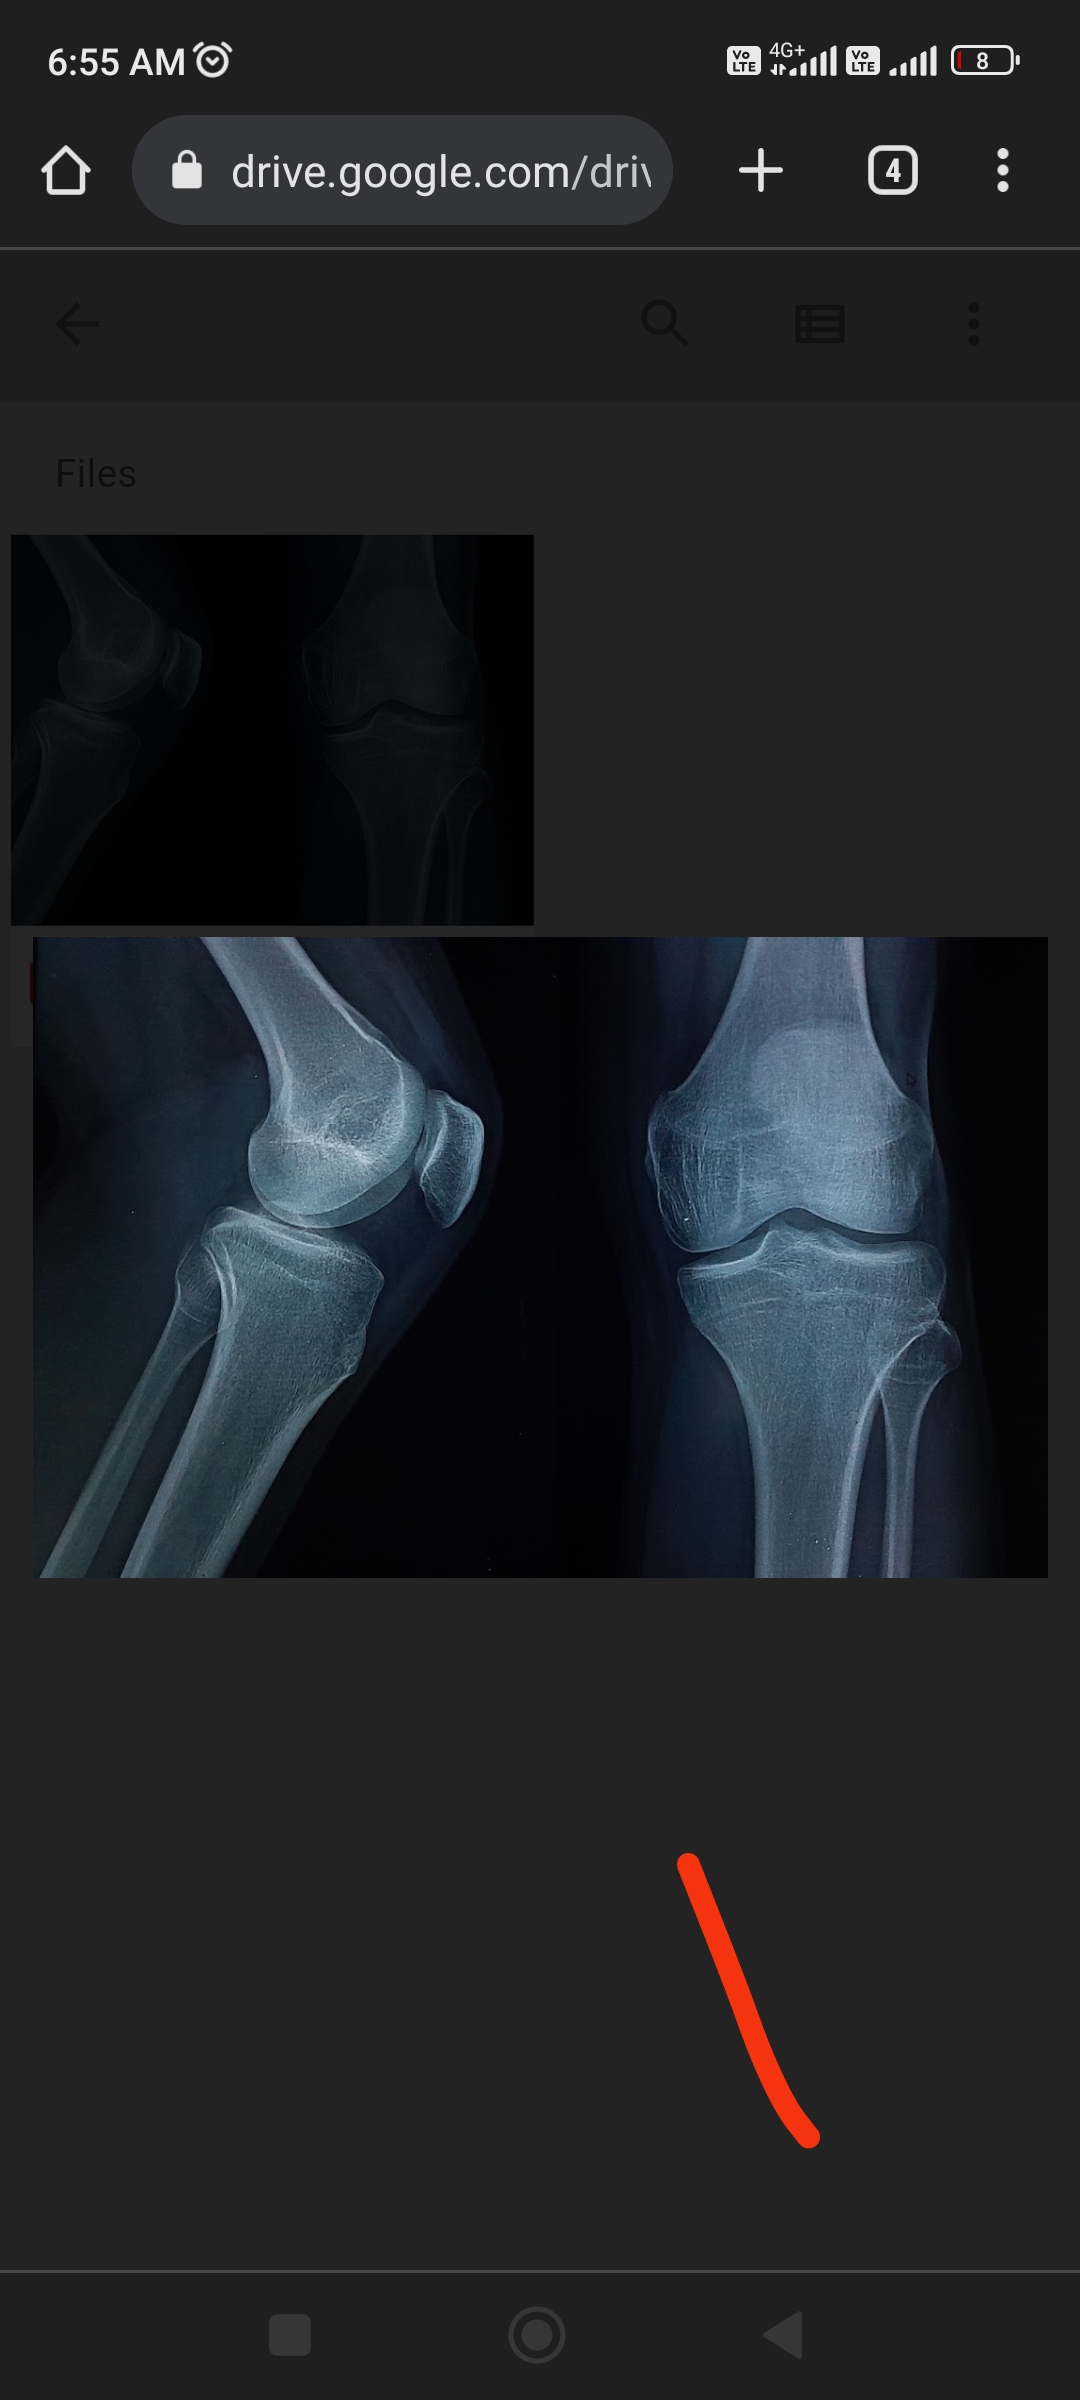

.Its literally closed lol, u wont grow more than a few cm

ye nvm ur right, i looked again, it looks fusedView attachment 2634501

This is how it will look like in better xray, and its closed lol,this is open with 4+ inch potentialView attachment 2634503

Looks almost entirely fused to me. You can still grow via other bones. Its also possible that the growth plates on the opposite side of your femur and tibia are open. Even if not, you can still grow via your spine.

It's the lighting nigga that's blurring the linesIts literally closed lol, u wont grow more than a few cm